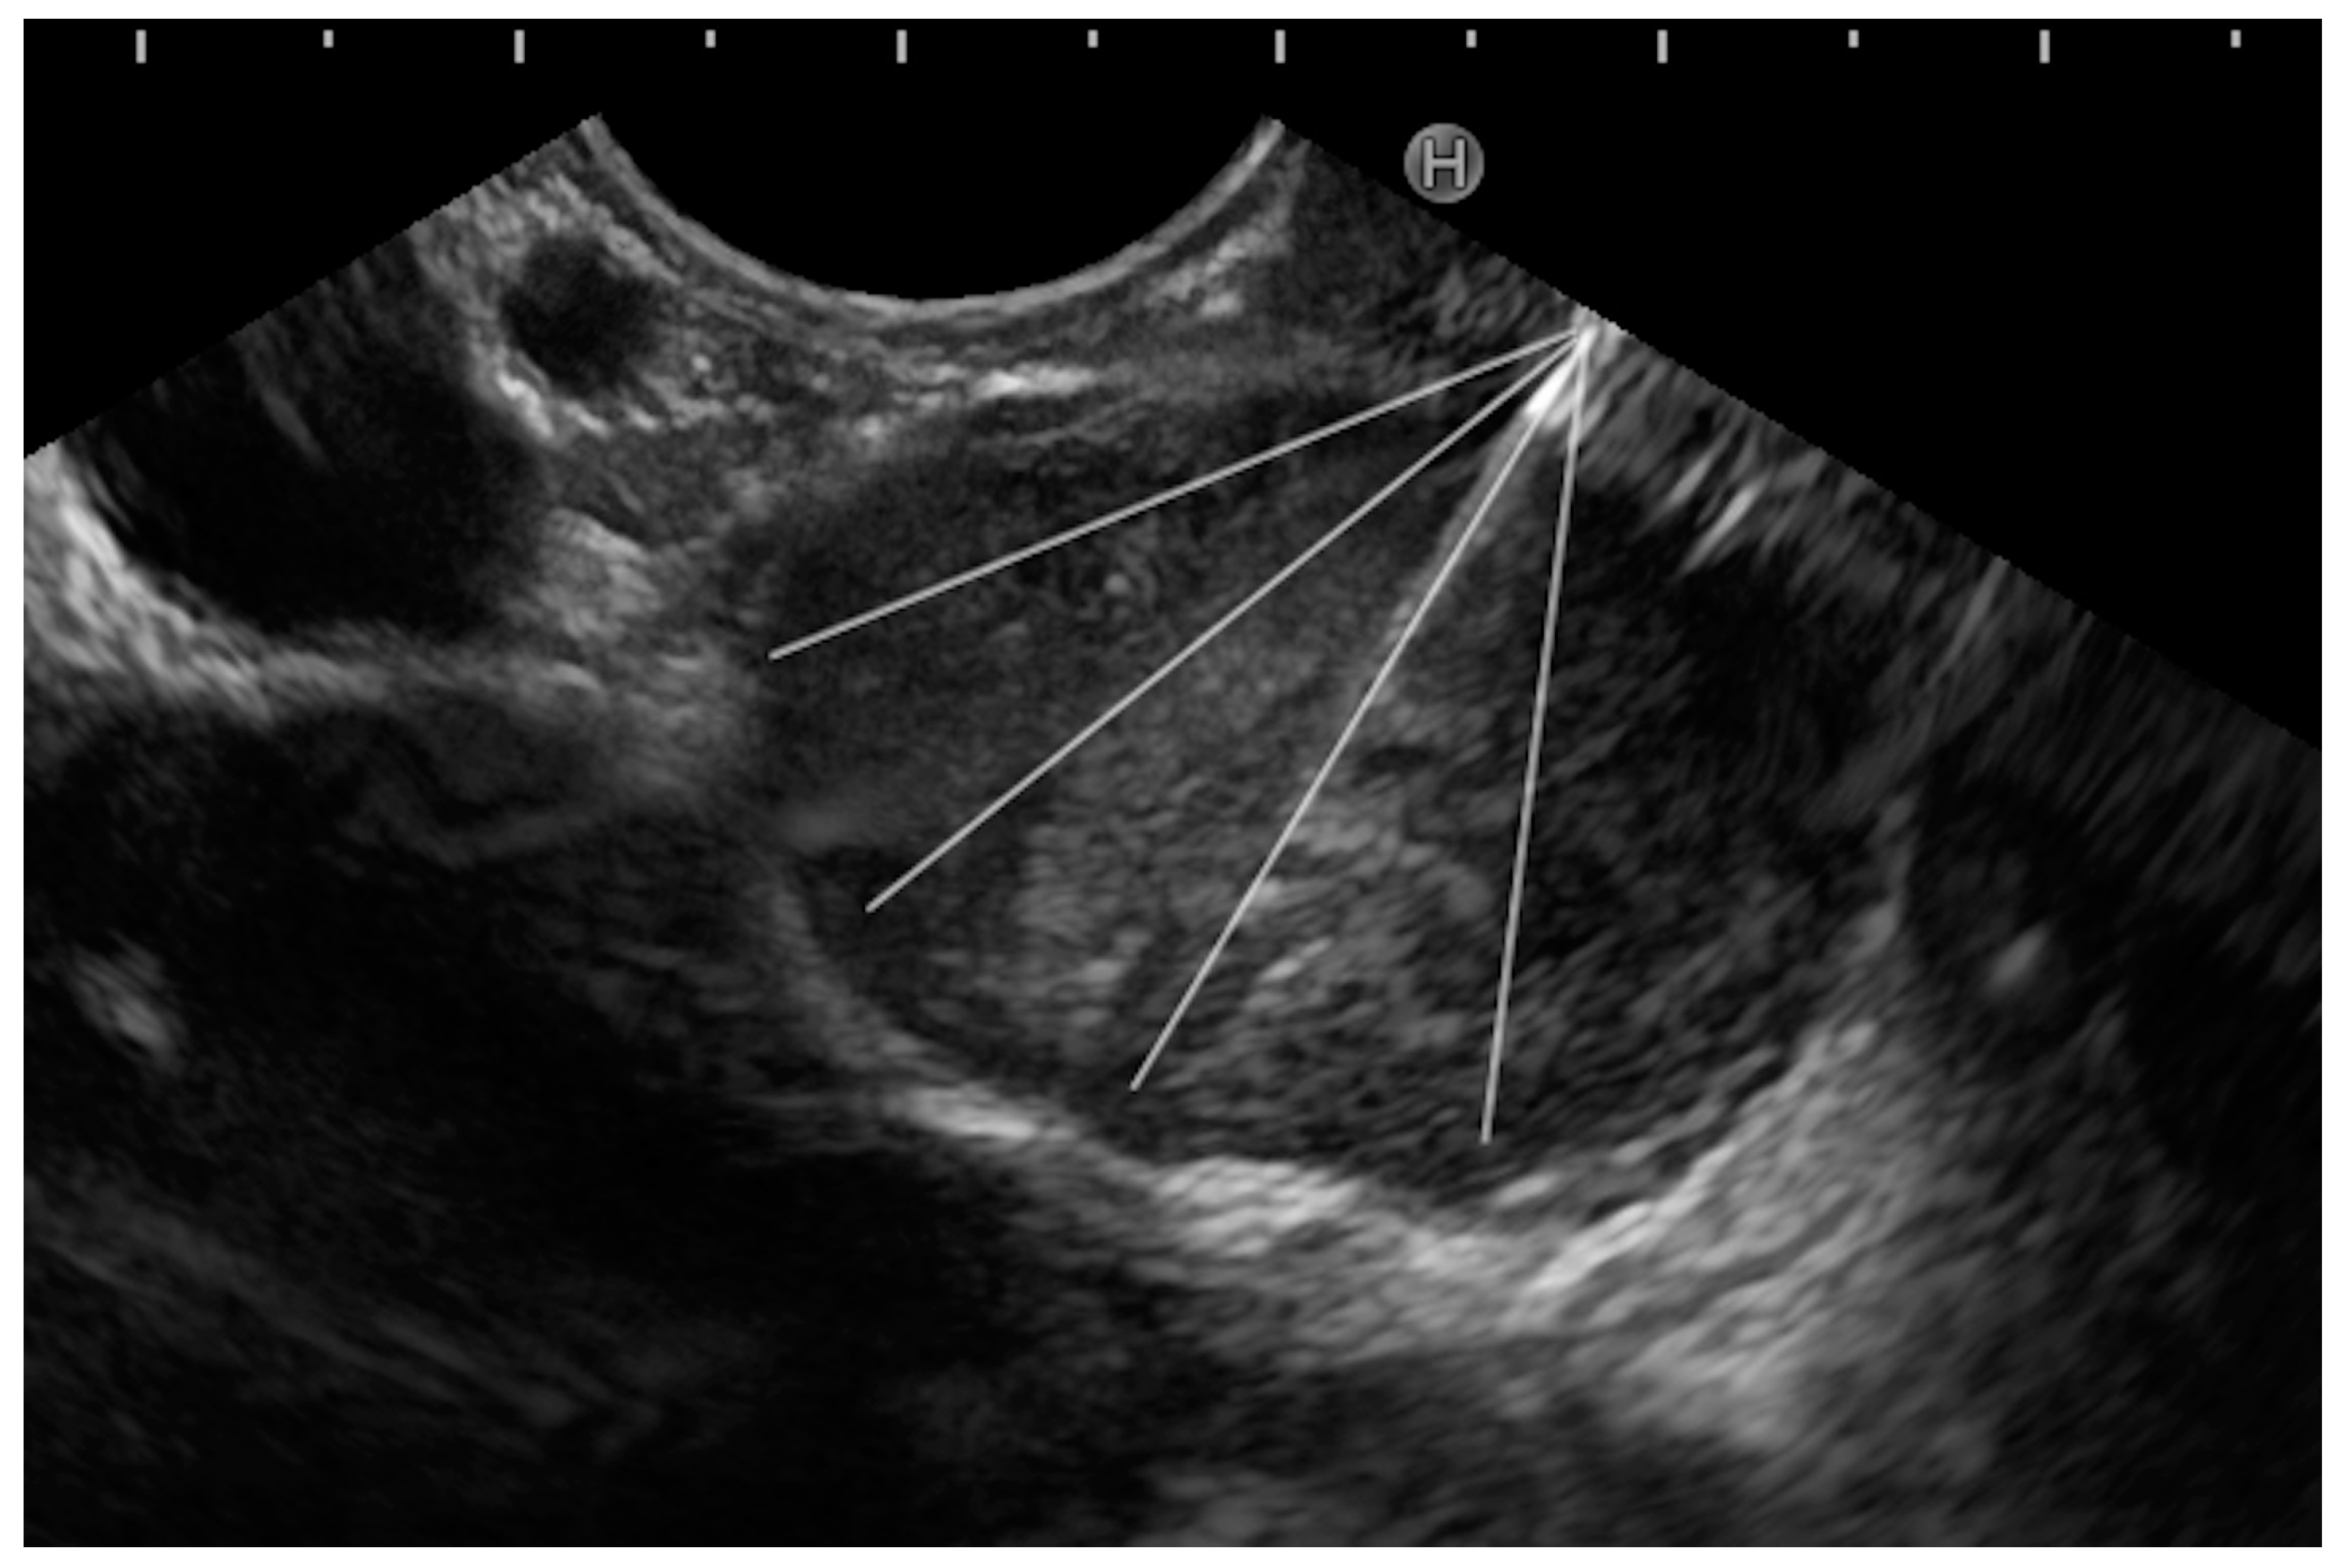

- Fanning technique: This technique entails the initiation of the biopsy from the left margin of the tumor mass, and the needle is “fanned” till the right margin is reached. The trajectory of the needle is altered using the up–down knob or the elevator. In this fashion, the needle is positioned at four different areas within the lesion, and four actuations are performed in each area (Figure 5). This is termed as the ‘4 × 4’ rule’.

Figure 5. Example of different directions (white lines) of the needle inside the lesion, resulting in sampling different regions of the tumor (fanning technique). - (c)